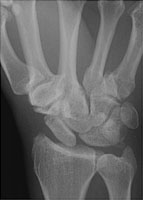

- Click on the image for a larger versionBPA radiograph of the wrist. This depicts the abnormal relationship between the scaphoid and the lunate.